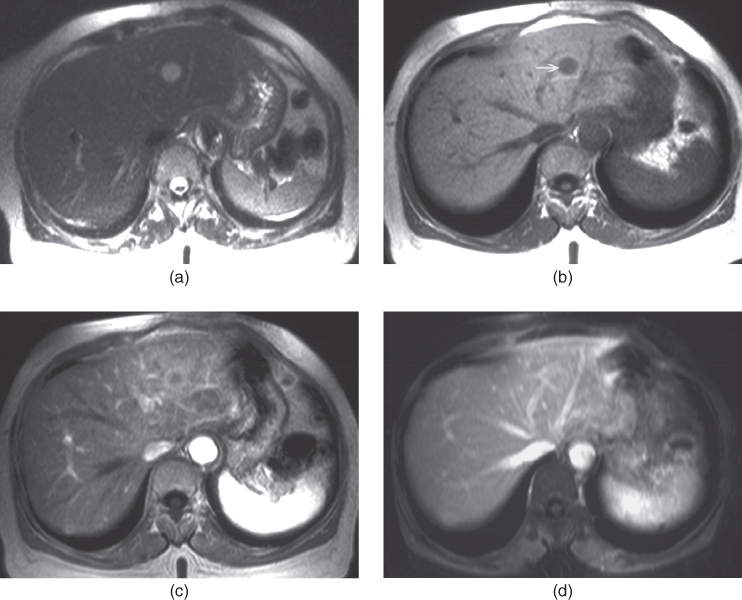

From pubs.rsna.org

Liver Metastases Correlation between Imaging Features and Endoscopic Ultrasound Liver Metastasis Overall, eus results were in accordance (moderate agreement) with ct or mri results for focal and metastatic liver lesions, with p < 0.001. The use of endoscopic ultrasound (eus) examination in the diagnosis and management of gastrointestinal tumors has evolved since its inception in the 1980s. And sample lesions as small as 5. Endoscopic ultrasound (eus) is an emerging imaging. Endoscopic Ultrasound Liver Metastasis.

From radiologykey.com

Liver metastases Radiology Key Endoscopic Ultrasound Liver Metastasis The use of endoscopic ultrasound (eus) examination in the diagnosis and management of gastrointestinal tumors has evolved since its inception in the 1980s. And sample lesions as small as 5. Endoscopic ultrasound (eus) is an emerging imaging modality with resolution suf cient to detect. Overall, eus results were in accordance (moderate agreement) with ct or mri results for focal and. Endoscopic Ultrasound Liver Metastasis.